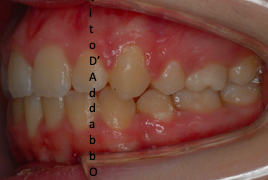

In alcune malocclusioni i denti superiori non coprono adeguatamente quelli inferiori con la presenza in alcuni casi di una beanza fra le due arcate. Questo può essere dovuto ad abitudini viziate come il succhiamento del dito, una deglutizione scorretta, una postura della lingua alterata o un problema scheletrico. In questo esempio il problema è associato ad una terza classe scheletrica.

prima

dopo – fase 1